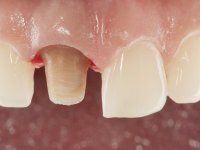

A pre-print was performed to make a crown in dual-cured resin. After a cross-section with a turbine, the infiltrated crown was removed with a microluxador. The dental stump was re-prepared to better define the shape and location of the cervical margin. It was necessary to place composite resin on the buccal surface of the provisional crown to improve its esthetics. The impression was made using a double-mix technique with two-viscosity, quick-setting silicones. In the laboratory, a crown with a ceramic-coated Zr infrastructure was made. After placing it in the mouth, we verified that the crown showed a greater translucency than the symmetrical one, not fulfilling our aesthetic goals. The ceramist had the opportunity to observe the situation in the clinic, collecting records for later rectification. The new crown was placed in the mouth and approved by the patient. The final cementation was done with resin-reinforced glass ionomer cement.